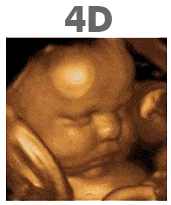

What is the difference between 2D, 3D, 4D and HD Live?

2D ultrasound is the standard black and white ultrasound image you will typically receive at your doctor’s appointment. 3D ultrasound images show much more detail of the baby’s facial features. 4D ultrasound shows the movement in the womb of your baby. Finally, HD ultrasound shows even more detail and a richer color.